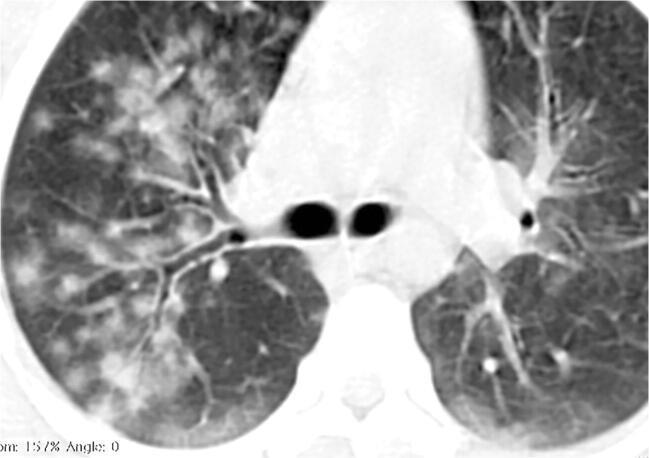

• Patchy bilateral GGO, Consolidations or both

• Peripheral and lower lung zone predominance

• Bilateral & multifocal GGO, +/Consolidations or both

• Halo sign

• Peripheral and subpleural

• Bronchovascular thickening

COVID 19

• Halo sign (Early)